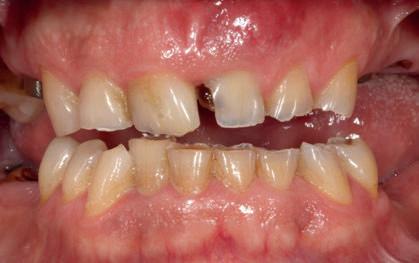

A PROPÓSITO DE UN CASO Paciente hombre de 52 años de edad que acude a la consulta demandando tratamiento implantológico para varias ausencias dentales y la restauración de los dientes remanentes (Figuras 1 y 2). El caso fue estudiado mediante modelos diagnósticos, exploración clínica y radiográfica.

Figura 1. Una imagen intra-oral mostrando la ausencia de piezas dentales en los sectores posteriores, la presencia de diferentes grados de desgastes dentales y raíces dentales remanentes.